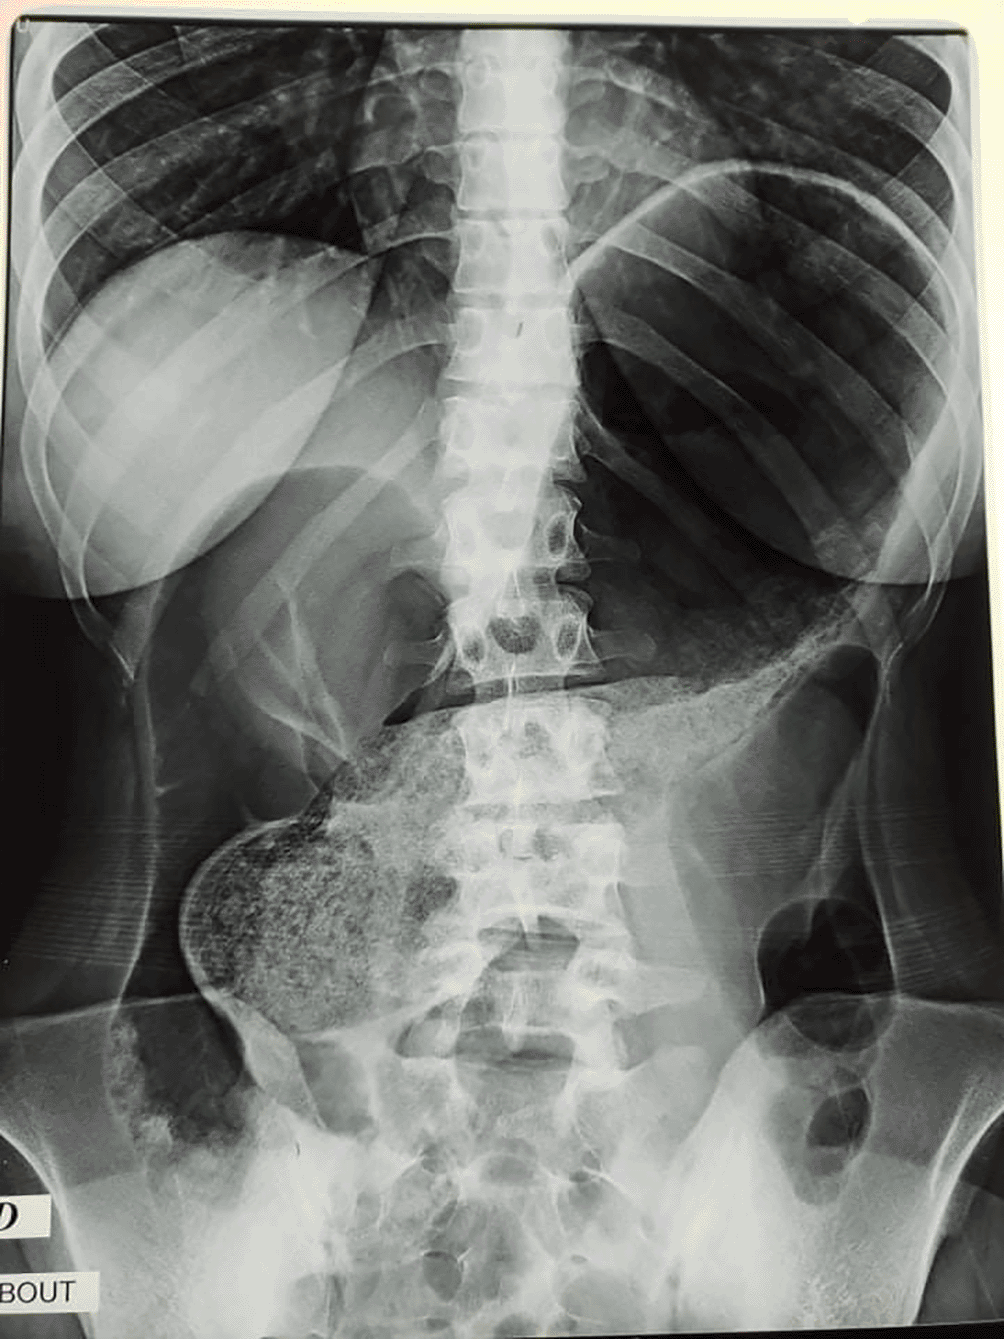

Abdominal X-rays were taken, and they revealed distension of a loop of the large bowel, with its long axis extending from the right lower quadrant to the epigastrium or left upper quadrant. Colonic haustral pattern was absent (Figure 1).